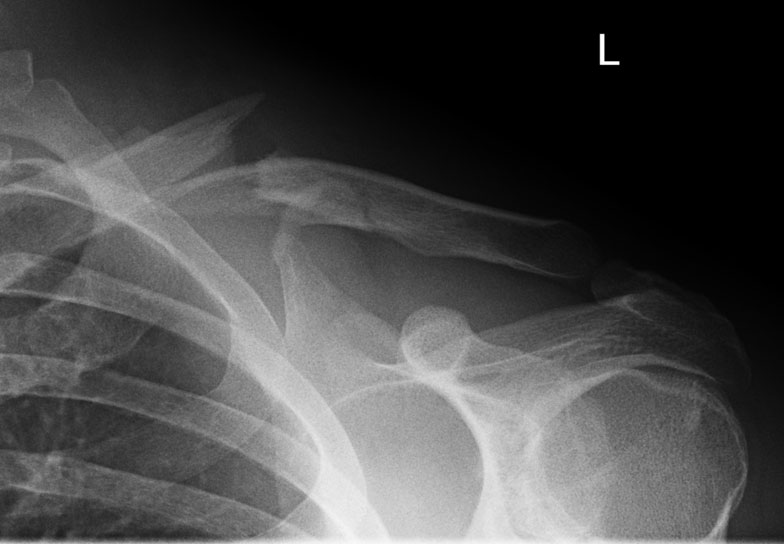

What do clavicle fractures look like on X-ray?

Below are examples of typical fractures that benefit from surgery.

Click an image to enlarge

A 15 year old female fell from her pushbike causing a displaced left mid-shaft clavicular fracture. Seen 5 days later, plate & screws inserted 2 days later.

Image

DIsplaced fracture before surgery

DIsplaced fracture after surgery

Move the slider to compare before surgery and after surgery